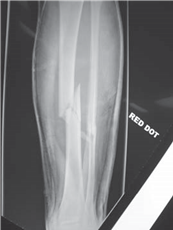

What do you see in these two radiographs?

T here is an AP view of the lower left leg showing multifragmented mid-shaft fractures of the tibia and fi bula, probably resulting from a high-energy impact. The chest radiograph suggests that there has been a signifi cant insult to the chest/lungs.

What do you understand by the term damage control orthopaedics (DCO)?

DCO is a planned and staged surgical strategy in the management of polytrauma patients to minimize the eff ects of the โsecond hitโ on an already limited physiological reserve. The โfi rst hitโ is from the injury and the bodyโs response to this injury, while the โsecond hitโ is produced by surgical intervention.

E vidence shows that, in certain patients, primary external fi xation of long bone fractures and secondary nailing improves outcome. There is a reduction in the incidence of multiple organ dysfunction syndrome (MODS) and adult respiratory distress syndrome (ARDS).